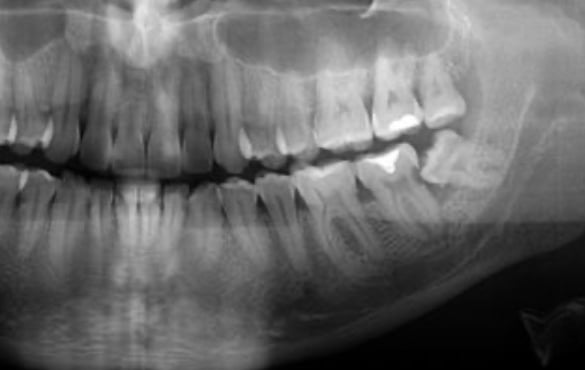

Pacientes Sistêmicos (com doenças crônicas, com diabetes, hipertensão, cardiopatias) e acamados muitas vezes apresentam mais risco de complicações orais. A falta de tratamento adequado pode transformar um problema dental em porta de entrada para infecções graves.

A cirurgia odontológica em pacientes sistêmicos e acamados e essencial para prevenir infecções , controlar dor e proteger a saude geral. Quando bem indicada e planejada, torna-se um procedimento de segurança, cuidado integral e qualidade de vida.